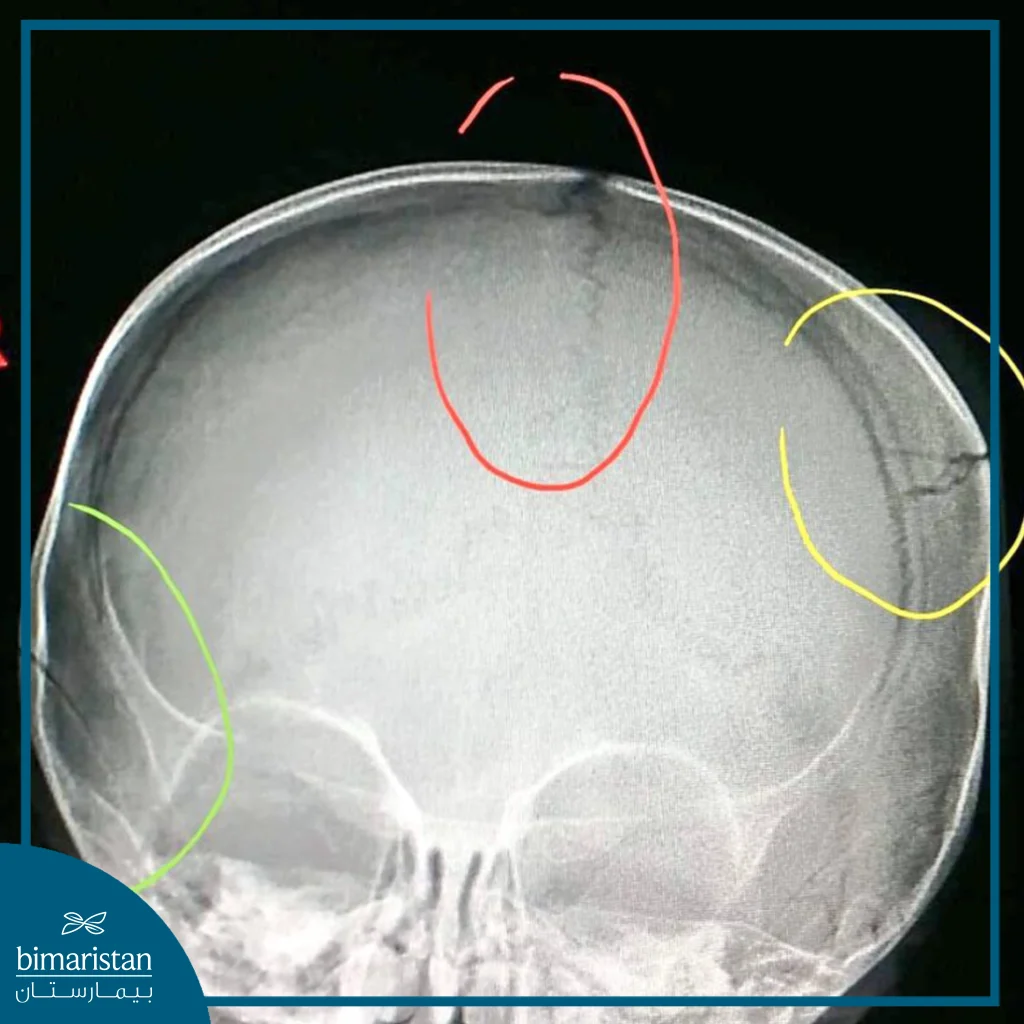

It is important to diagnose a skull fracture quickly and accurately, as serious injuries can cause side effects that may be fatal or lead to permanent disabilities, as these injuries are usually diagnosed using imaging techniques such as X-rays or MRI to determine the extent of the damage and make the appropriate decision in order to treat skull fracture in adults in particular, and in some cases the fracture can be simple, while in other cases it may require surgical intervention to repair the damaged bones.

- Initial assessment of the case: The medical team evaluates the case by conducting the necessary tests, such as X-rays or CT scans, to determine the type of fracture and its impact on the brain, and brain function is also checked to make sure there is no compression or damage to the nerve tissue.